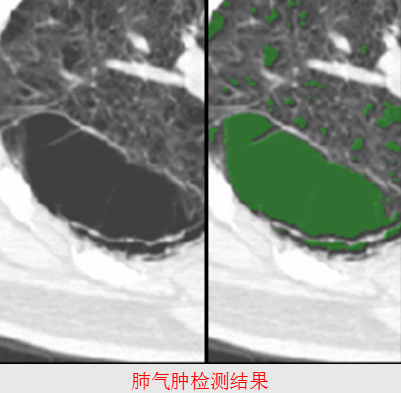

肺气肿检测

包括肺气肿区域检测和肺气肿定量分析,其定量分析指标有肺气肿体积、肺气肿区域百分比、严重程度和是否存在肺大泡。

肺气肿的CT影像表现为灰度值低于肺实质的黑色大泡。一般采取基于图像灰度的方法检测肺气肿。